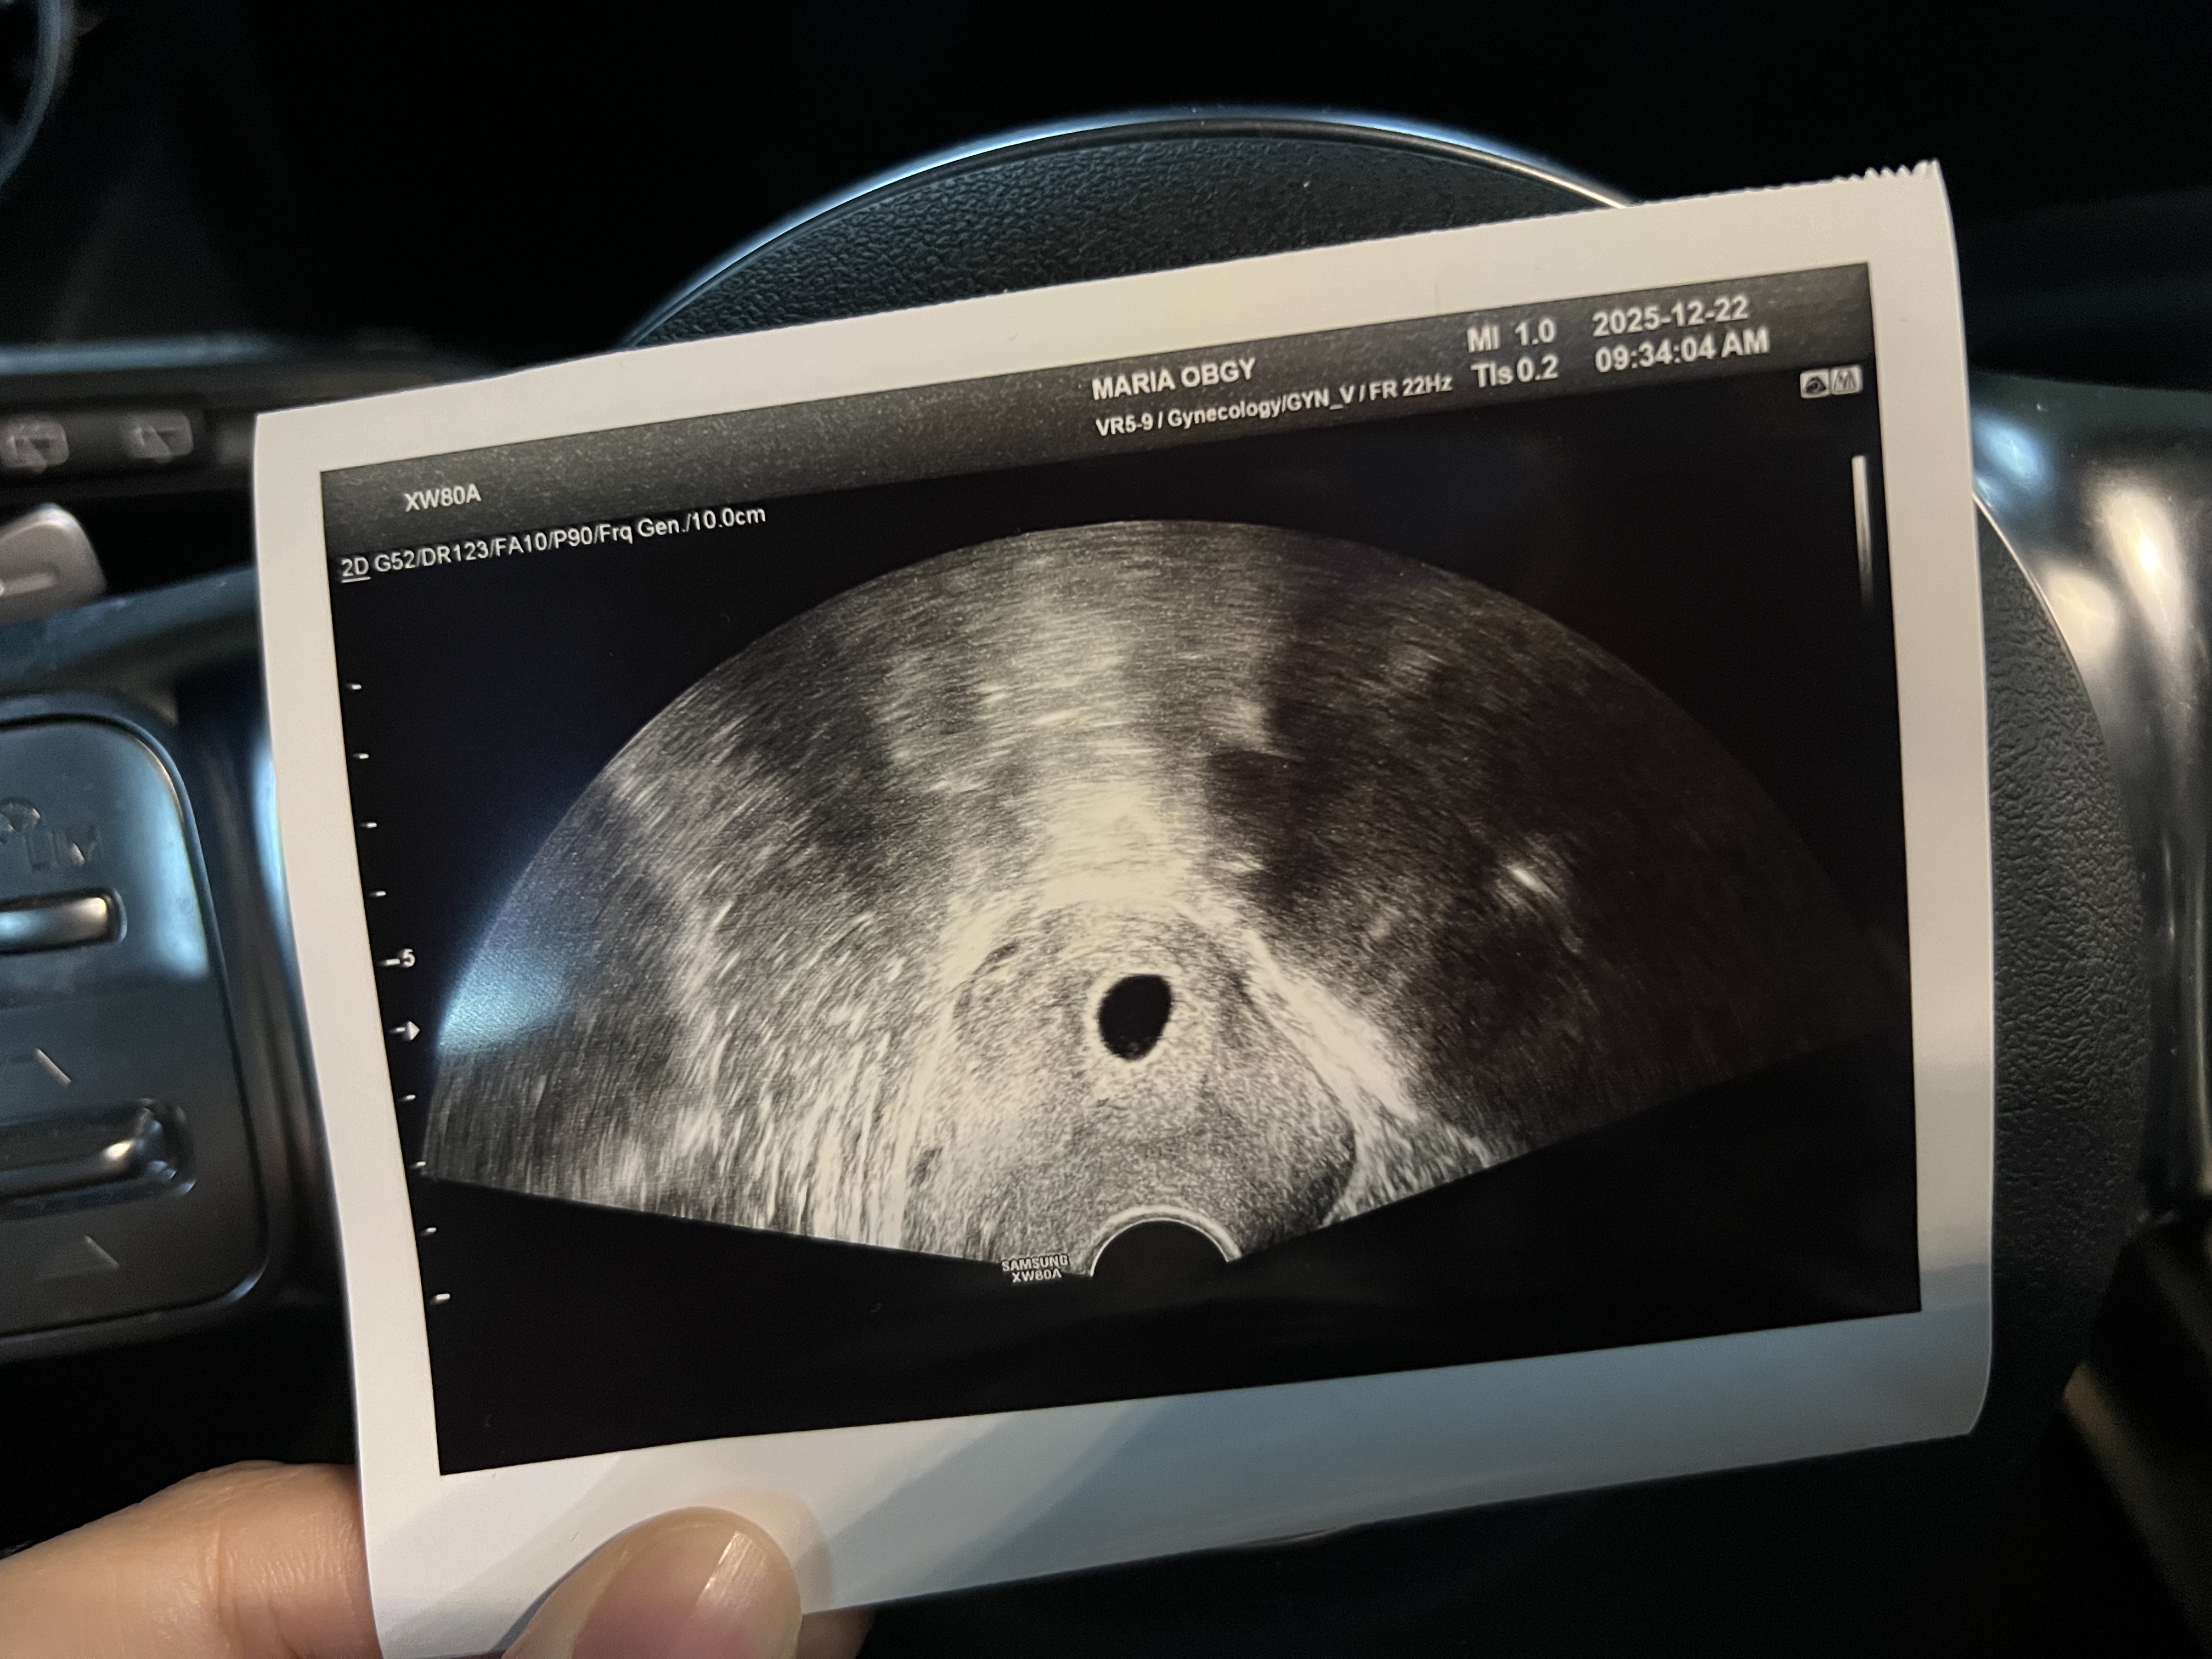

11월 28일 오전에 5일배양 냉동이식 진행해서 12.8일 1차피검 142/12.15 2차피검 3290 으로 피검사 통과했고, 12.22일 오늘 초음파 보러갔는데 아기집은 보이고 난황이랑 아기가 안보인다는데 괜찮을까요?.. 이식날짜로 계산하면 오늘이 6주 1일차인데.. 3년전 시험관때도 6-7주차때 잘못되서 소파술 한 경험이 있어서 불안하고 무섭네요..